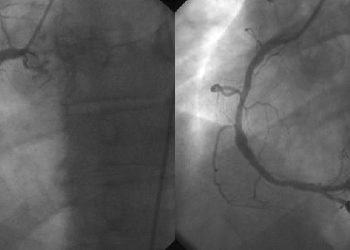

Older patients with STEMI and cardiogenic shock benefit from percutaneous coronary intervention

1. In this retrospective analysis of patients 75-years or older with ST-elevation myocardial infarction (STEMI) and cardiogenic shock, use of ...